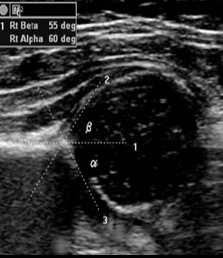

Identify this image.

Gluteal muscles

Labrum

Acetabulum

Ilium

Triradiate cartilage

Ischium

Femoral head

Which angle is used to evaluate hip dysplasia?

Alpha

What are the classifications for hip dysplasia?

Type I or normal: Alpha angle > 60

Type II or normal from newborn to three months: Alpha angle 44 - 60

Type III or dislocation: Alpha angle < 43

Type IV or gross dislocation: Alpha angle not measurable